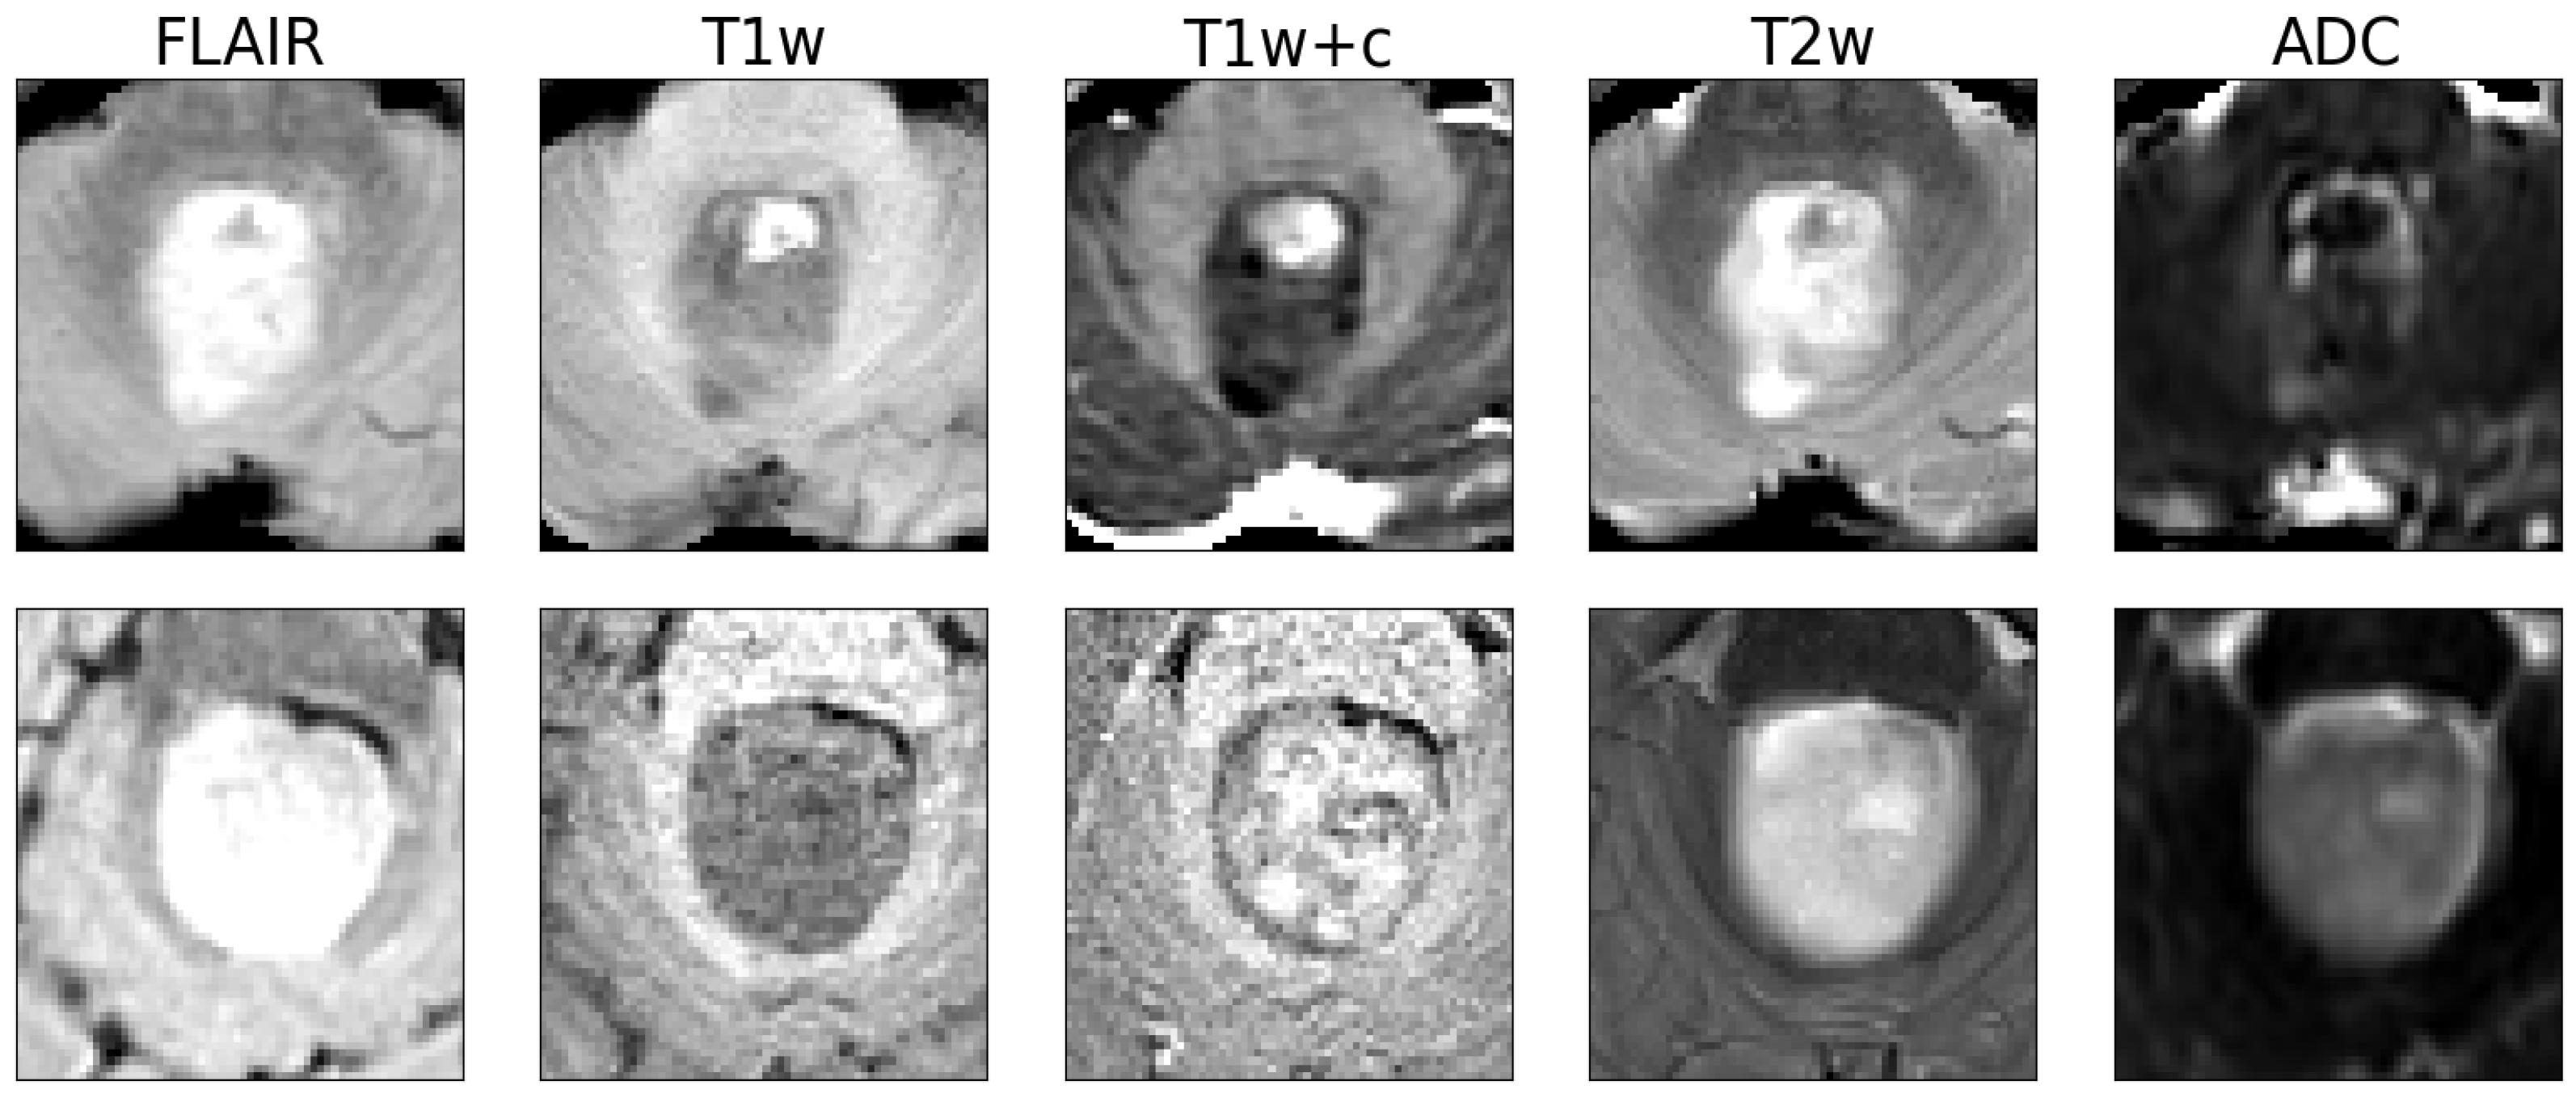

2.1. Data Set